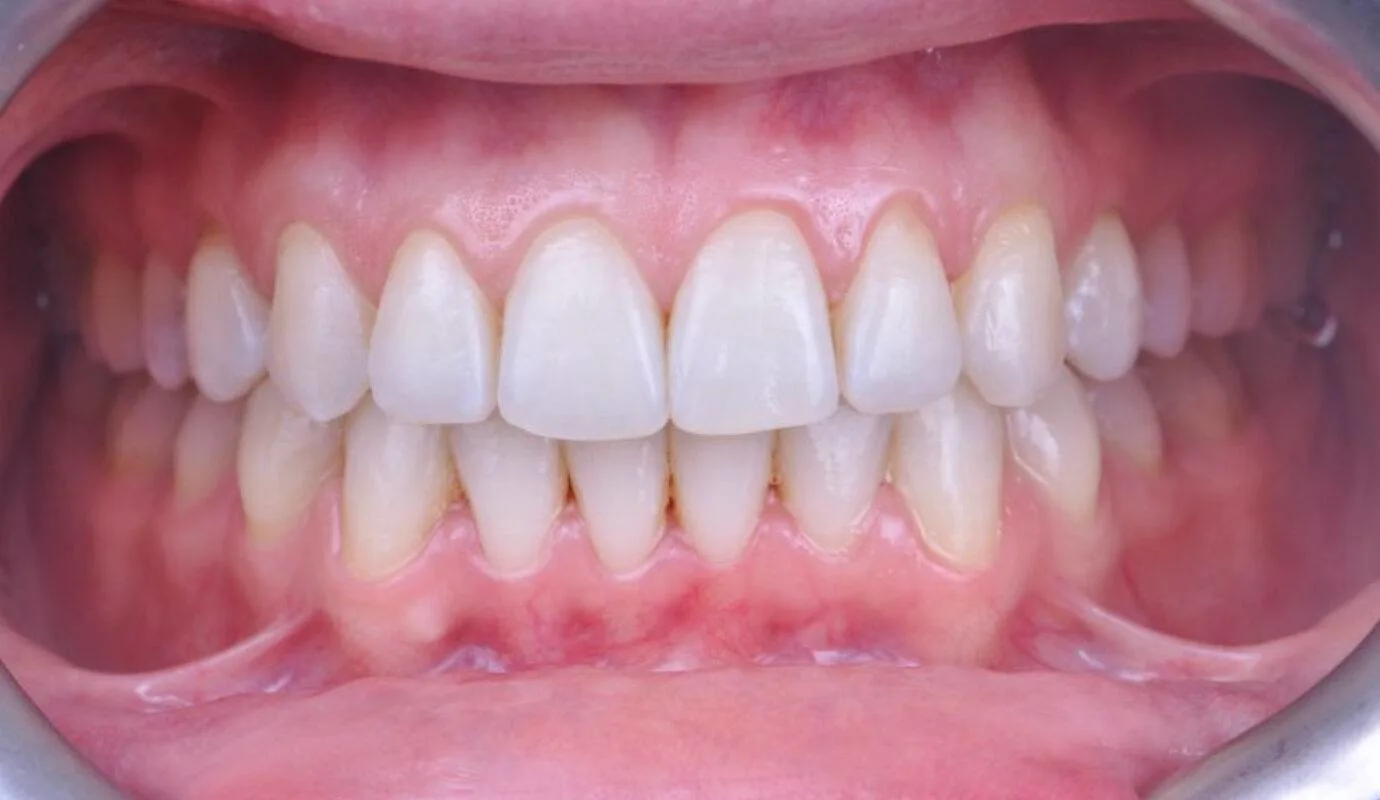

Before overcrowding treatment at SmileBox Clinic After overcrowding treatment at SmileBox Dental Clinic